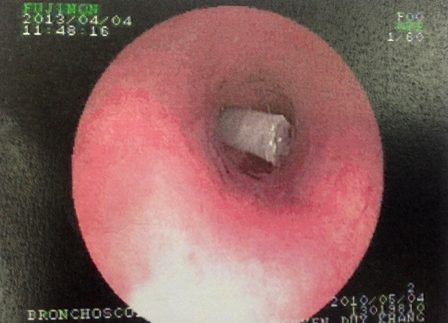

Sau khi hội chẩn nhanh, bác sĩ quyết định điều trị bằng kháng sinh và kháng viêm tích cực để đẩy lùi tình trạng ho khò khè. Ngay sau đó, bệnh nhi được chỉ định nội soi kiểm tra phế quản. Đường đi của ống nội soi đã bị cản ngang bởi một mẫu nhựa trắng hình ống dính đầy đàm nhớt. Dị vật nhanh chóng được gắp ra ngoài và xác định đó là chiếc béc thổi gắn phía trong đầu kèn để tạo âm thanh khi thổi. Sau khi gắp được dị vật ra ngoài tình trạng của bé K. đã ổn định.